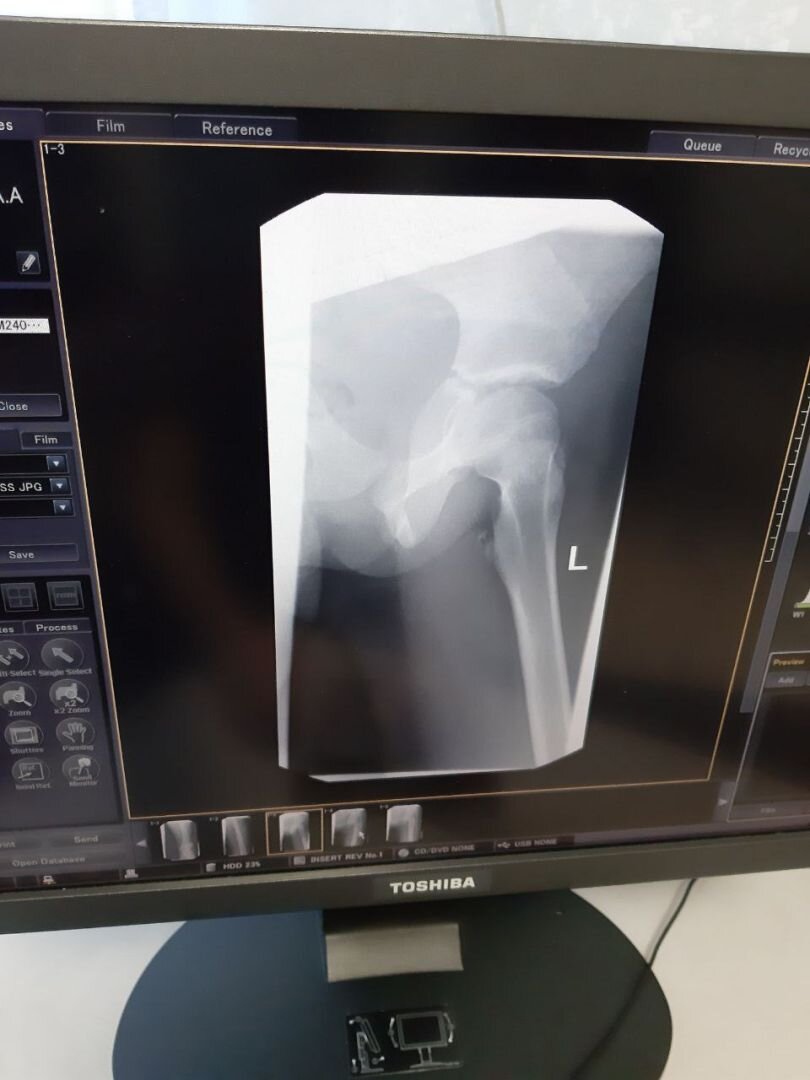

«Сначала всё было неплохо, но при новом режиме катаниякресло в котором сидел мой ребёнок начало сильно подбрасывать, в результате чего мой ребёнок 4 раза очень сильно ударился о поручень (который является единственной страховкой данного аттракциона), в результате чего была получена травма — УШИБ МЯГКИХ ТКАНЕЙ ЛЕВОГО БЕДРА, ОСТЕОЭПИФИЗИОЛИЗ МАЛОГО ВЕРТЕЛА (ЭТО ПЕРЕЛОМ ЗОНЫ РОСТА)», —написалав соцсетях мать пострадавшей девочки.